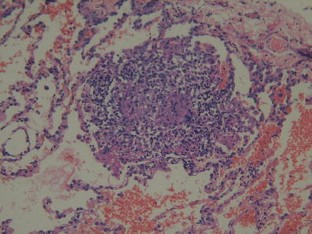

Takayasu’s arteritis presenting with bilateral pulmonary granulomatosis

Takayasu’s arteritis (TA) is a vasculitis characterized by inflammation and obliteration of intermediate to large-size arteries. We report a case of Takayasu’s arteritis with a presentation of bilateral pulmonary nodular infiltrates in a 21-year-old man. An open-lung biopsy showed characteristic changes of extra-vascular granulomatosis. To our knowledge, this has not been described previously in the literature.

Fig. 2